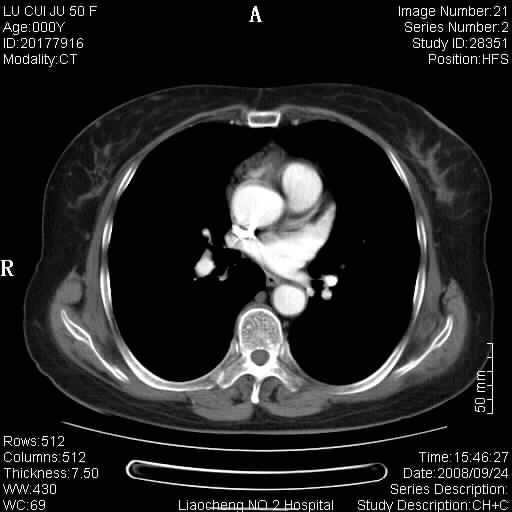

标题: CT15870:F50Y,纵膈占位,是不是胸腺瘤,请各位高手讨论。

临床表现为重症肌无力;ct增强扫描可见前纵膈胸腺部位弥漫性簇状软组织节结灶,不知道是不是胸腺瘤,请各位高手讨论。

考虑胸腺增生

考虑胸腺增生!!

胸腺组织残留

为未退化胸腺